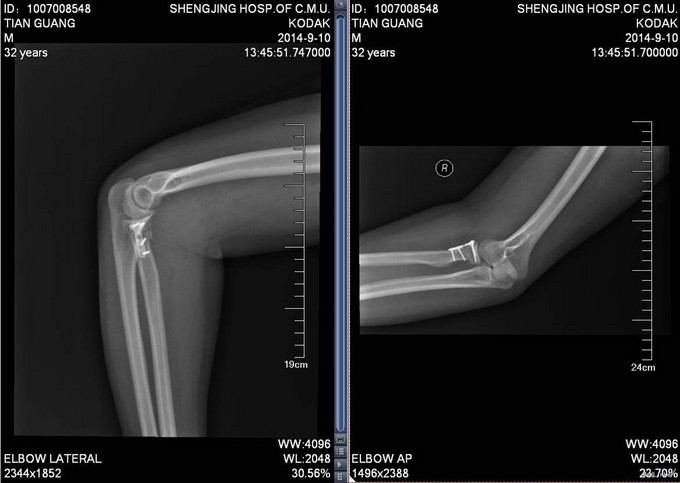

入院后完善检查,查无手术禁忌症后行右桡骨颈骨折切开复位内固定术,术后抗炎、接骨等对症治疗。术后第二天康复锻炼。术后2天一次换药,14天后出院。